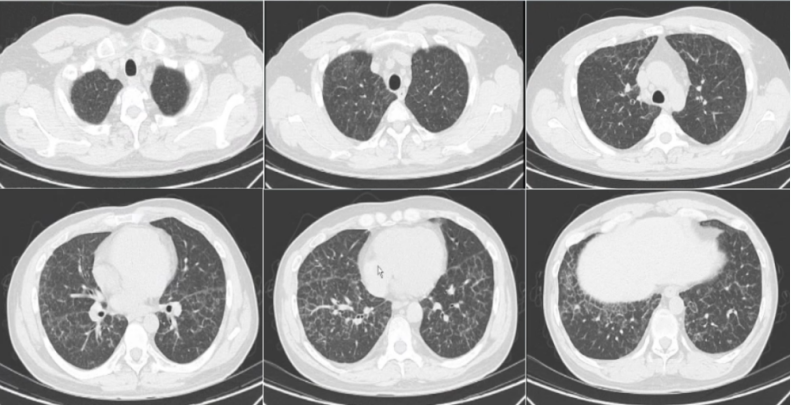

4月22日,患者胸闷减轻,咳嗽有痰,为白痰,精神较前好转,高流量氧疗(氧浓度45%),心电监护示一般生命体征在正常范围内。体格检査:胸壁多发斑丘疹,双肺湿啰音较前减少。胸部CT示:两肺弥漫性密度增高影,大面积实变影,铺路石征(图2)

图片

图2  患者胸部CT(2024-04-22)